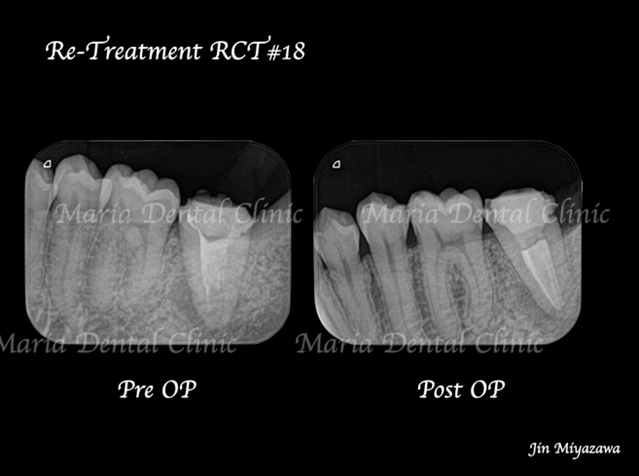

に対する、精密根管治療のアプローチ(再根管治療)_治療前のレントゲン画像1.jpg)

に対する、精密根管治療のアプローチ(再根管治療)_治療前のレントゲン画像2.jpg)

前医にて根管治療を終了したが、痛みと違和感に改善がないため来院された患者様です。前医では樋状根(といじょうこん)の為、これ以上の治療はできないと言われ、抜歯を勧められていました。

に対する、精密根管治療のアプローチ(再根管治療)_治療前後比較治療前のレントゲン画像.jpg)

に対する、精密根管治療のアプローチ(再根管治療)_治療前後比較治療後のレントゲン画像.jpg)

バイオセラミックにて根管充填を行いました。レントゲン写真からは根尖まで良好に隙間なく根管充填を行っていることが確認できます。

1回目の治療終了後、2週間後には違和感等は感じられないようにまで回復しました。